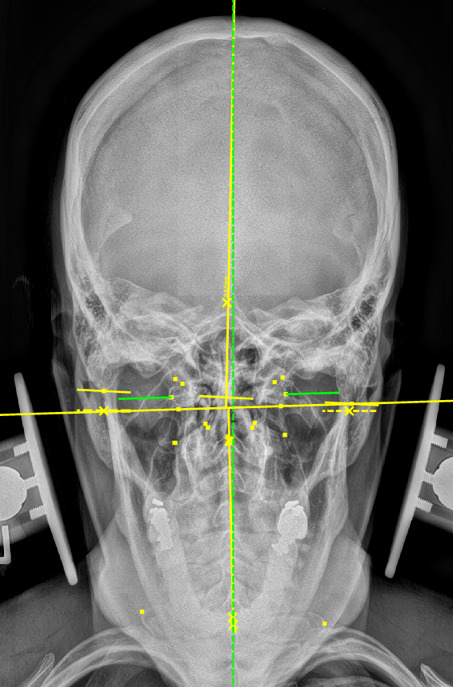

During the initial examination, the chiropractor evaluates the patient’s postural findings, including standing head tilt, head rotation, shoulder height comparison, hip height comparison, lower neck deviation, and supine leg-length inequality. The chiropractor will then take 3 radiographic images of the CCJ minimum to view the alignment in a projected 3-dimension. These images are the cervical neutral lateral (sagittal plane), the nasium (frontal plane), and the vertex (transverse plane). A series of measurements are graphed on the radiographs to assess for alignment. Then, the Orthospinology upper cervical procedure provides a calculation and vectored angle based on these measurements to reduce the misalignment. The chiropractor will use this angle to administer the adjustment to the CCJ. Immediately after the adjustment, the chiropractor evaluates the postural findings for correction. If it has improved, the chiropractor repeats the nasium and vertex views to observe for structural correction. If the postural findings do not improve, the chiropractor may administer a subsequent adjustment before the post-imaging is taken.12